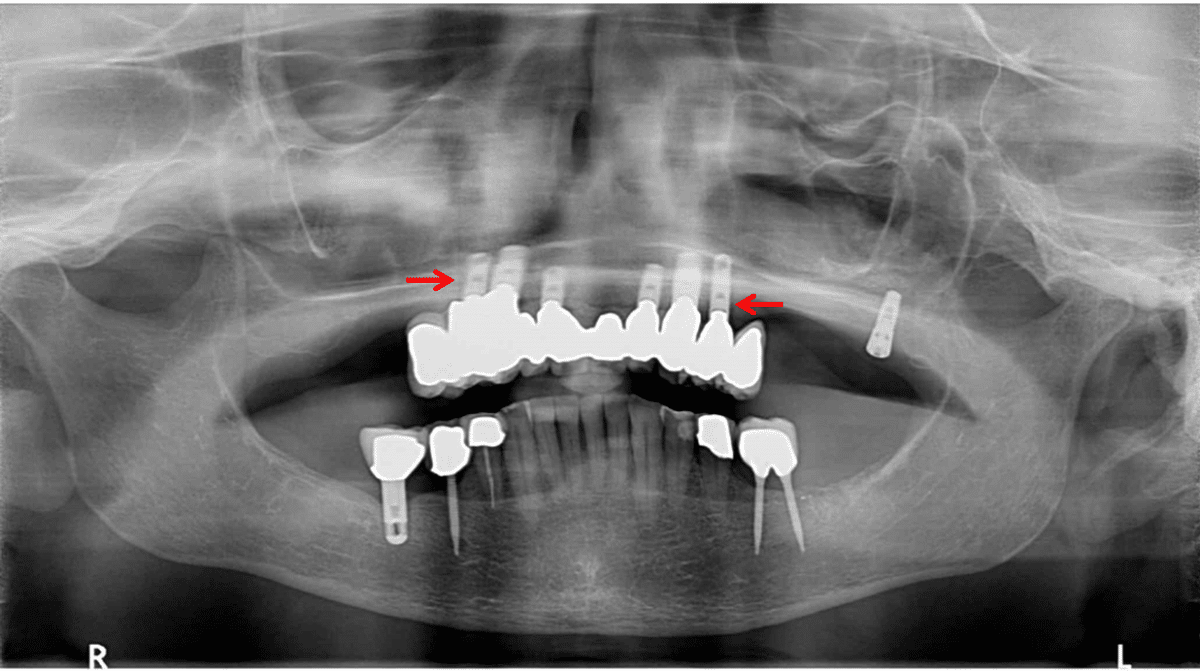

As the interim crowns were being completed, dental implants were strategically placed to provide support for a full arch of fixed restorations. Seven implants were positioned to provide optimal support distribution and long-term stability.

After implant osseointegration was complete, a comprehensive full arch of custom-crafted crowns was fabricated on the implants. The crowns were designed to provide optimal function, natural appearance, and support for healthy gingival tissue.

The patient was completely reborn with a full arch of crowns seated on seven implants. She avoided denture wear entirely during the treatment process and now has permanent fixed restorations that provide complete function and esthetics.